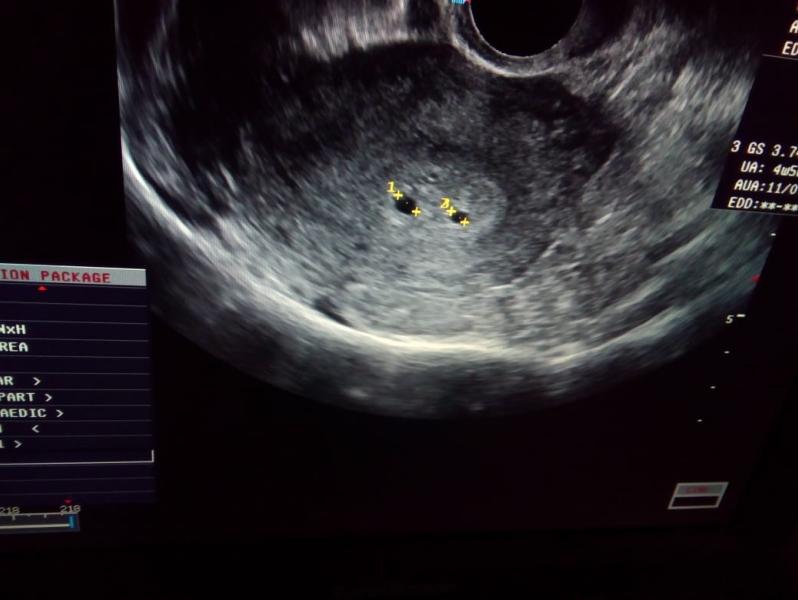

Ну вот.... я одна на миллион😫 Сегодня была на повторном УЗИ. Результат: в матке 1 живой развивающийся плод. Возраст по мес и узи ровно 8 недель. Второй плод рассосался...😥

Доктор посмотрел результаты первого узи и сказал, что в первый раз не ошиблись, было! Было у меня 2 ребеныша...

А фото своих двойняшечек я распечатаю и буду рассказывать своему одному из них, что был у него когда-то брат или сестренка двойняшка, а теперь-Ангел Хранитель...